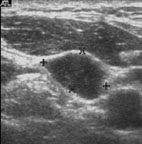

蔡先生因在左頸有腫塊而到耳鼻喉科門診就診(圖5),頭頸部的局部檢查除了左頸有界限糢糊不清的腫塊外其它包括鼻咽部(圖6)並沒有明顯異常,以頭頸部超音波檢查發現淋巴結預測值高於7分(圖7),超音波導引下細針穿刺細胞學檢查懷疑是轉移性鼻咽癌後,接受內視鏡鼻咽部切片證實為鼻咽癌。由於蔡先生超音波導引下細針穿刺細胞學檢查,避免了過去常見的頸部腫塊的切片手術。蔡先生接受放射腺治療後,腫塊即消失,因此可見頸部腫塊的切片手術對於鼻咽癌的診斷治療是不必要的。

圖7. 頭頸部軟組織超音波檢查,惡性淋巴結預測值高於7分,超音波導引下細針穿刺懷疑是轉移性鼻咽癌,後由鼻咽部切片證實為鼻咽癌